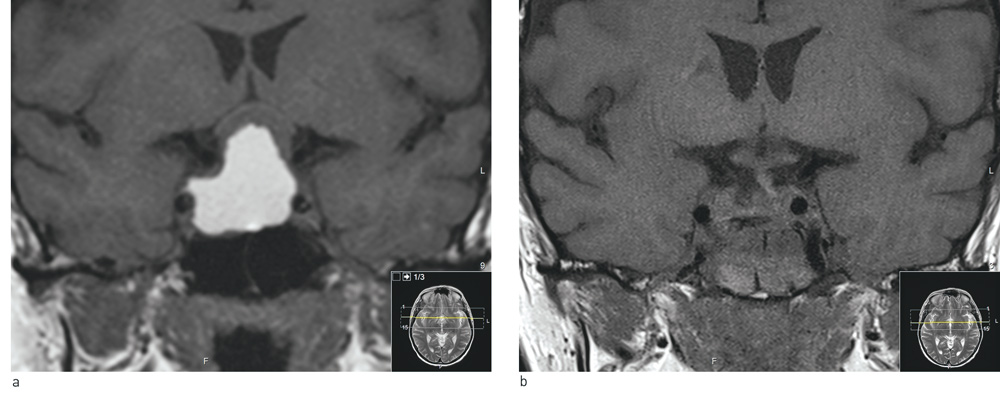

Ved nevrooftalmologisk vurdering før operasjonen var korrigert skarpsyn 1,6 for høyre øye og 0,25 for venstre øye. Pasienten leste Ishiharas fargeplansjer litt nølende for høyre øye og klarte ingen plansjer for venstre øye. Synsfeltet testet med terskelperimetri (fig 2a) viste en bitemporal reduksjon i sensibilitet, men med overvekt venstre øye. Venstre pupill hadde lett svekket direkte lysrefleks. Ved oftalmoskopi virker venstre synsnerve lett avbleket sammenlignet med høyre, som ved lett optikusatrofi. Nevrologisk status for øvrig var upåfallende.

Pasienten opplevde rask postoperativ normalisering av synet. Ved kontroll hos øyelege fem måneder etter operasjonen var korrigert skarpsyn 1,25 for begge øynene. Hun leste nå Ishiharas fargeplansjer for begge øynene, men fortsatt lettere for høyre enn for venstre. Terskelperimetri (fig 2b) viste betydelig bedring av tidligere bitemporal reduksjon i sensibilitet.